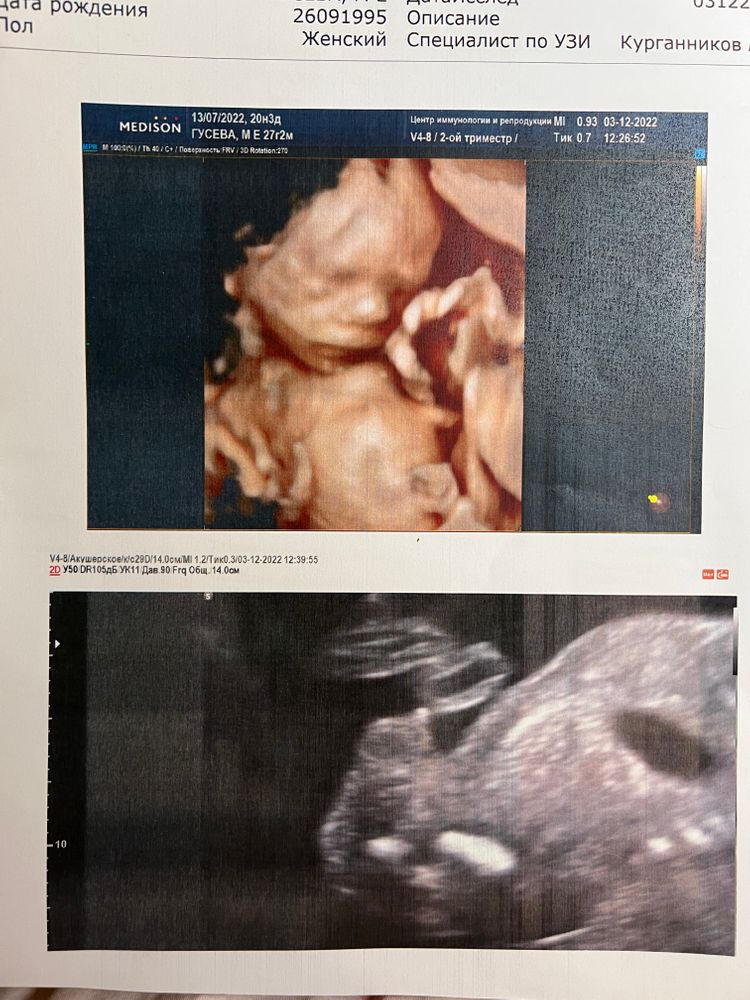

2 скрининг в 20.3 недели

Ну вот. Половина беременности позади. Наконец-то дождалась я второго скрининга. В целом, все хорошо - все соответствует нормам. Подтвердили мальчика (хотя уже никто и не сомневался)))), но .... поставили низкую плацентацию. Сказали, что ничего пока делать не надо, возможно поднимется.

Сладкий пирожочек наш, мы тебя очень любим и ждем!